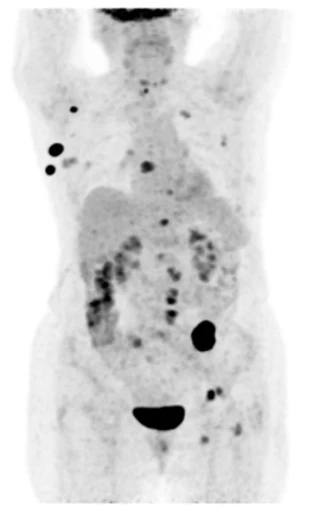

Это специализированное комбинированное устройство однофотонной эмиссионной компьютерной томографии/компьютерной томографии (ОФЭКТ/КТ) для осуществления различных томографических, кардиологических, онкологических и неврологических обследований. ОФЭКТ/КТ система ANYSCAN SC Mediso идеально подходит для 2D и 3D исследований и характеризуется большой производительностью и широким кругом решаемых проблем.

Совместное использование КТ и ОФЭКТ обеспечивает получение функциональной информации на молекулярном уровне и анатомической картины, с их последующим совмещением.